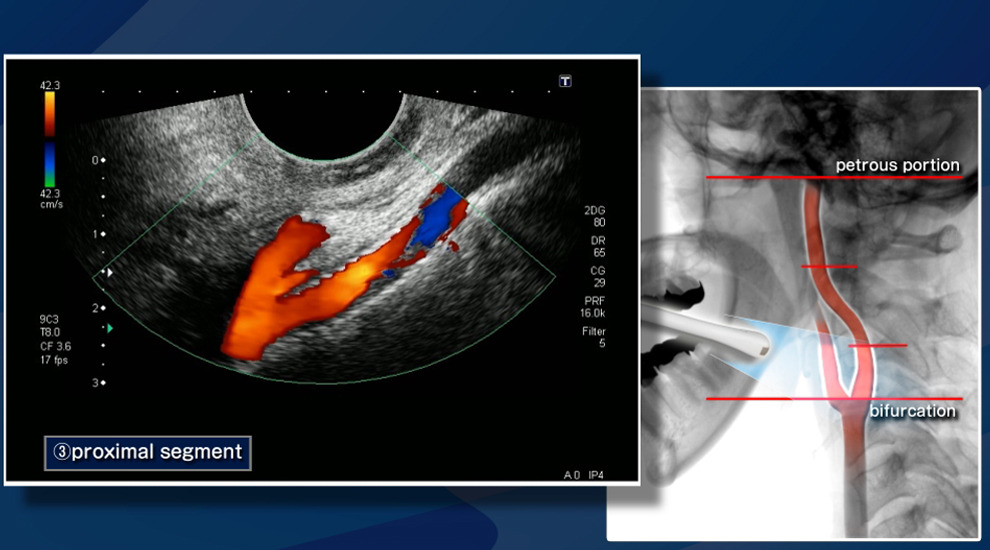

경동맥 초음파는 목 부위에 위치한 경동맥을 대상으로 초음파 장비를 사용하여 혈관 내부의 상태를 확인하는 검사입니다. 경동맥은 심장에서 뇌로 혈액을 공급하는 중요한 혈관으로, 이 혈관의 상태를 확인하는 것은 뇌졸중과 같은 심각한 질환을 예방하는 데 중요합니다. 경동맥 초음파 검사는 비침습적인 방법으로 혈관 벽의 두께, 플라크(혈전) 존재 여부 등을 파악할 수 있어 혈관 질환을 조기에 진단하는 데 큰 역할을 합니다.

- 의료진이 탐촉자를 목 부위에 대고 초음파 영상을 촬영합니다. 이 과정에서 혈관 내부의 상태와 혈류의 흐름을 확인하게 됩니다. 통증은 전혀 없으며, 전체 검사 시간은 약 15~30분 정도 소요됩니다. 검사 도중 의료진은 혈류의 속도와 방향을 확인하고, 혈관의 상태를 실시간으로 평가하게 됩니다.